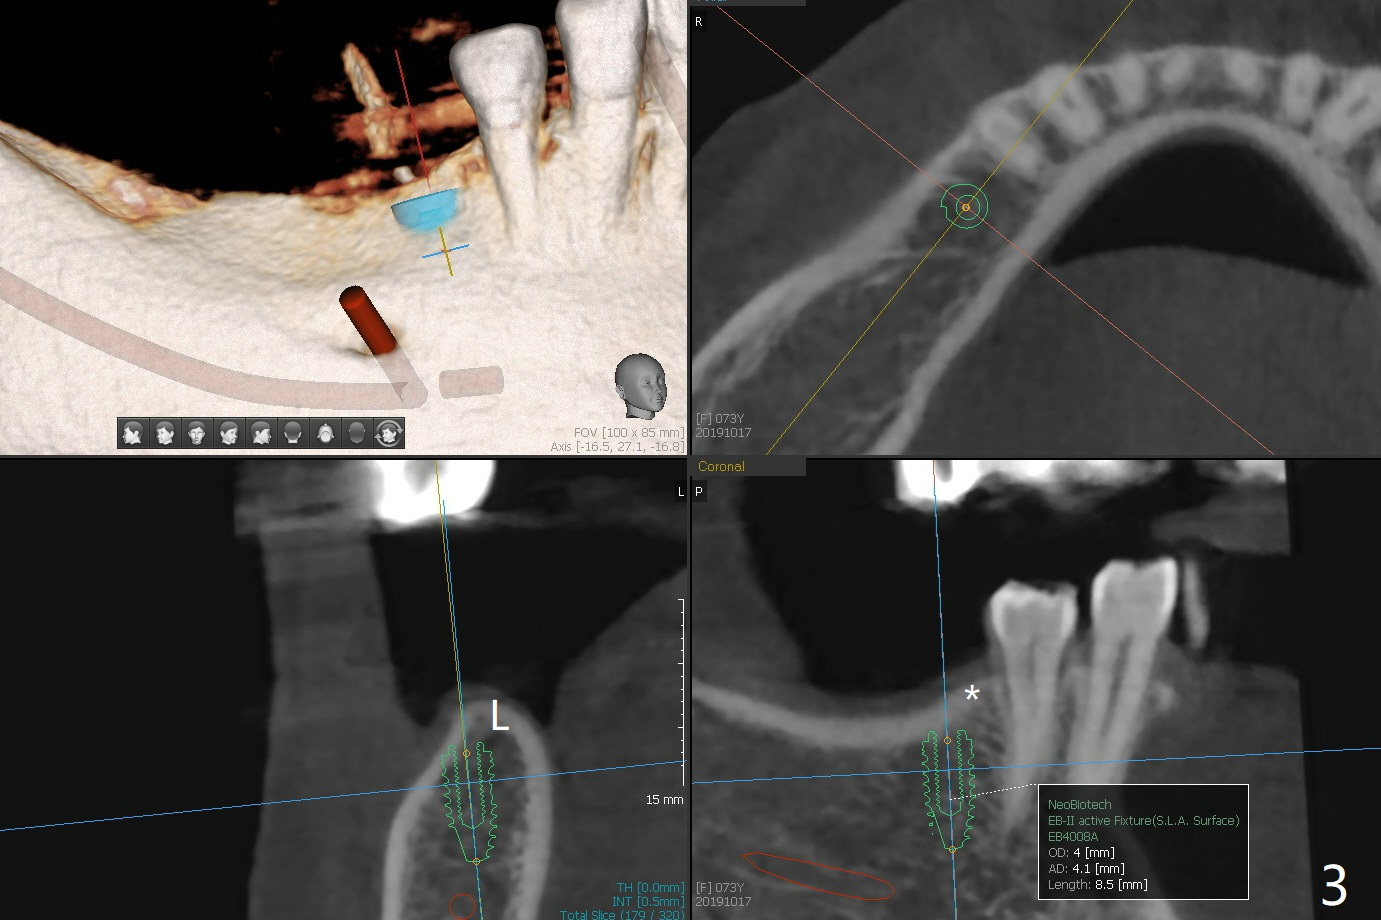

A 73-year-old woman has interest in implants at #19 and 29 (Fig.1). The ridge is not even, higher mesio(*)lingually (L, Fig.2,3). After implant placement, use profile drill (5.5 or 6.0 mm) to facilitate healing abutment placement.